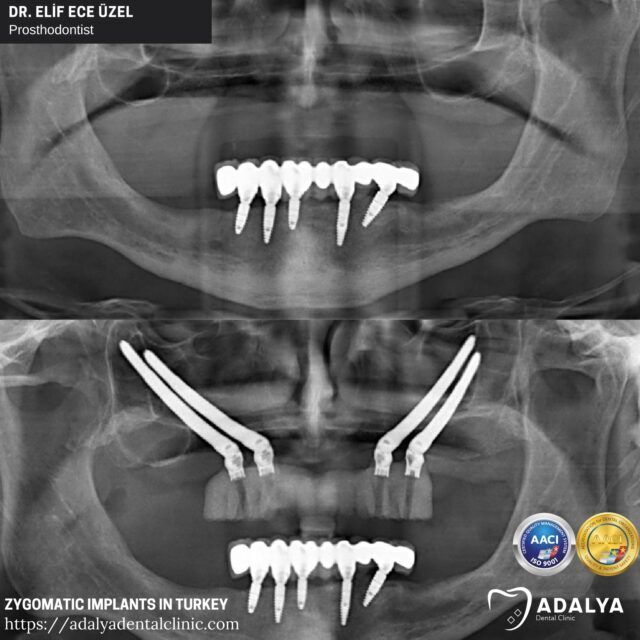

Zygomatic implants are longer than traditional dental implants, allowing them to anchor into the cheekbone (zygoma) instead of the jawbone. This alternative technique eliminates the need for bone grafting and lengthy healing periods, providing a quicker and more streamlined process.

Zygomatic implants are a revolutionary dental solution designed to address severe cases of tooth loss or bone loss in the upper jaw. Unlike traditional dental implants that rely on the jawbone for support, zygomatic implants are anchored into the cheekbone (zygoma), a stronger and more stable structure.

The length of zygomatic implants, which can range from 30 to 55 millimeters, allows them to extend beyond the upper jaw and into the cheekbone, providing a secure and reliable foundation for dental prosthetics. This game-changing technology has opened up new possibilities for individuals who were previously deemed unsuitable for traditional implants due to inadequate bone volume or quality.

To determine if you are a candidate for zygomatic implants, your dentist or oral surgeon in Turkey, Antalya will conduct a thorough evaluation, which may include a comprehensive dental examination, X-rays, and advanced imaging techniques like CT scans. These diagnostic tools will help assess the condition of your jawbone and cheekbone, as well as identify any potential anatomical considerations that may impact the placement of the zygomatic implants.